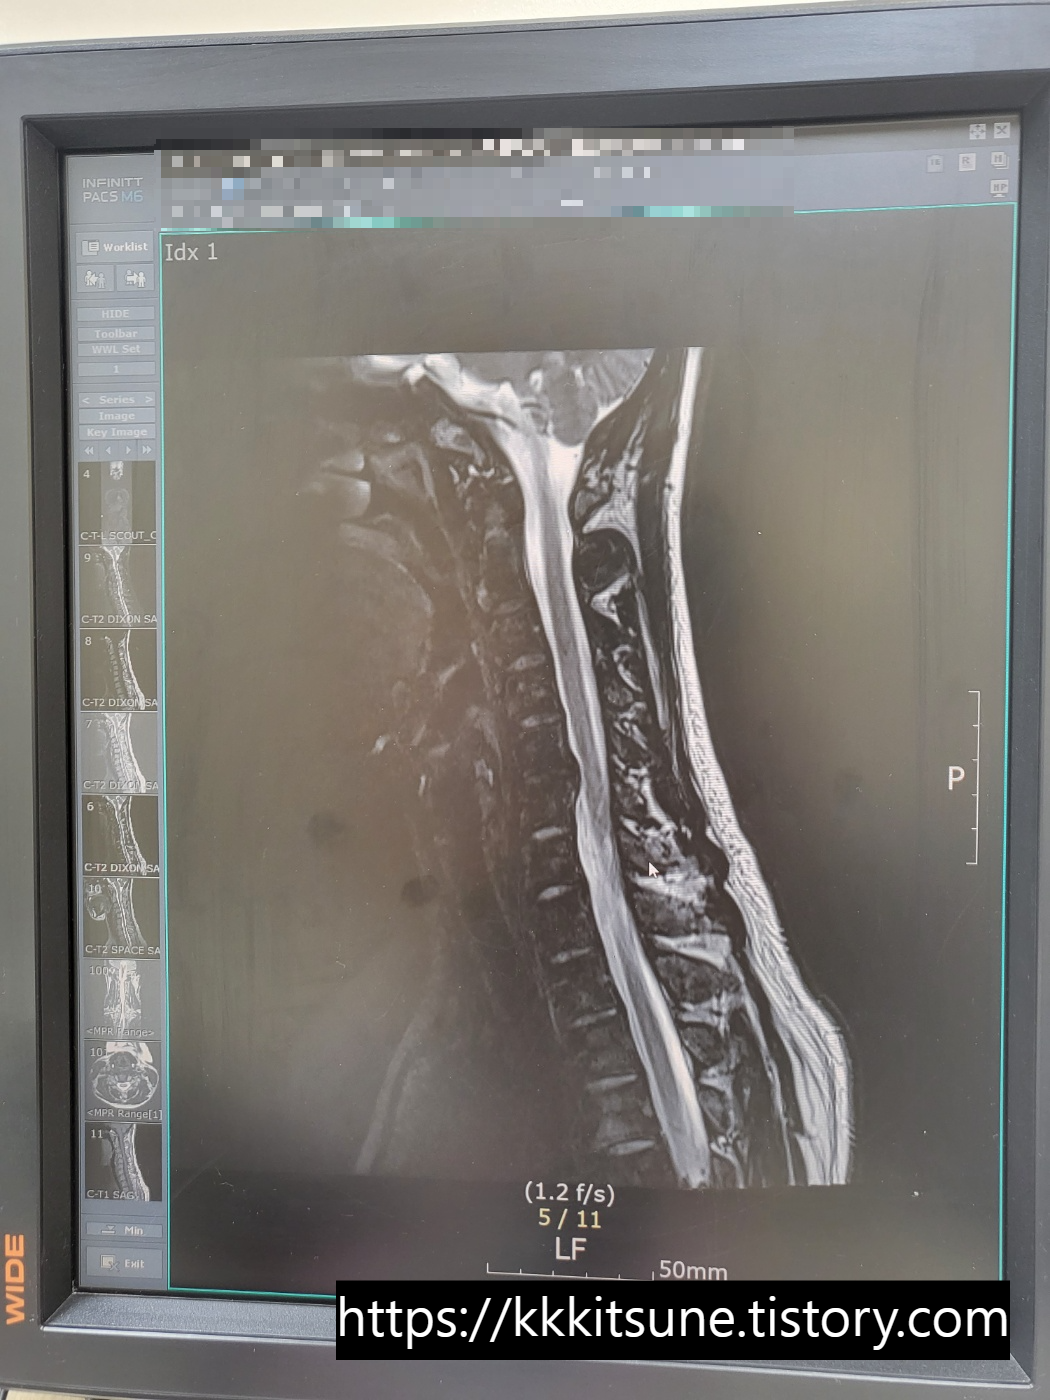

어제 찍은 MRI와 작년 수술 직전에 찍은 MRI를

비교해서 띄워주시면서 설명해 주셨다.

설명 없이 보기만 해도 차이가 너무 극명해서

진짜 다양한 감정이 교차했다.

왼쪽 사진에서는 튀어나온 디스크 때문에

신경이 거의 찔릴 뻔할 정도로 심각했다.

오른쪽 사진에서 뼈가 까맣게 뿌옇게 된 부분이

유합해서 고정시켜놓은 곳이다.

확실히 신경 길이 넓어지고 목이 일자로 펴졌다.

수술 전 사진이 누워서 찍은 MRI라는 것이

믿을 수 없을 정도로 역C자가 심한 것도 충격이었다.